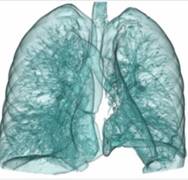

320排螺旋CT具备16cm宽覆盖探测器,实现动态容积扫描,360度的各向同性采集能力及[email protected]%密度分辨率的量子探测器,一次心跳全心脏采集,一圈扫描器官成像,一次检查完成多重任务,实现真正的动态容积体灌注及心脏、神经一站式检查;西门子Flash炫速CT扫描系统,具备两套同时旋转的X射线球管及探测器,实现了43cm/s的极快CT扫描速度和75 ms的时间分辨率,完成全胸扫描仅需0.6秒,使得患者做心脏扫描时无须食用β-受体阻滞药,亦无须屏气,并可实现低于1mSv的超低辐射剂量,配置第二代双能量、宽151级纯化能谱,组织鉴别能力进一步提高,可开展多达10余种双能量成像应用。